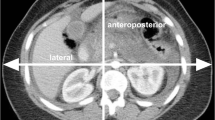

Patient data collection

Two study coinvestigators (L.K. and M.K.K.) created a fillable, multi-sheet Excel file (Microsoft Inc.) for collecting patient examination data in a uniform format. Each participating site was asked to provide information on 90 consecutive patients for the following 6 CT protocols (15 patients per each type of examination): routine head CT, head CTA, routine chest CT, CT-PE, routine abdomen/pelvis CT, and multiphase liver CT. The following information was recorded from each participating site: hospital name, patient age, gender, weight (kg), height (cm), body mass index (BMI, kg/m2), clinical indication for each CT examination, scan parameters (number of scan phases and kV for each scan phase), contrast information [concentration (mgl/mL), volume (mL), flow rate (mL/s), and technique for estimating scan delay (fixed, test bolus, and bolus tracking)] and CT radiation dose descriptors (CT Dose Index volume for each phase (CTDIvol in mGy) and Dose Length Products (DLP in mGy·cm) for each scan phase. We estimated the total iodine load per CT examination (product of the volume of ICM and contrast concentration) and iodine delivery rate (IDR, production of the flow rate of ICM injection, Per the World Health Organization classification of patient size based on BMI, we divided the patientsinto four groups underweight (BMI < 18.5 kg/m2), normal range (BMI 18.5–24.9 kg/m2), overweight (BMI 25–29.9 kg/m2), and obese groups (BMI > 30 kg/m2).